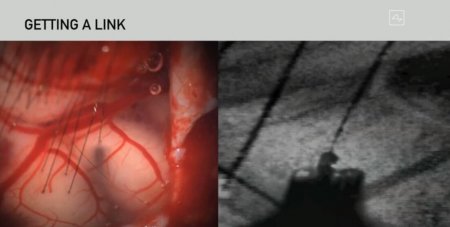

В рамках презентации публике была показана свинья с устройством Neuralink, который был вживлен за два месяца до мероприятия. То, как подключенные к мозгу электроды считывают активность свиного мозга, можно было наблюдать в режиме реального времени, в ходе прямой трансляции. Для вживления устройство был использован робот-хирург, только как он работает, Илон Маск не рассказал. Больше всего интересно то, что как он проводит операцию — автоматически, или управляется человеком? Также хотелось бы узнать, к каким областям мозга подключаются электроды. Ранее сообщалось, что они крепятся к областям, ответственным за движения и ощущение внешних раздражителей.

Прямая трансляция с мероприятия велась на YouTube-канале Neuralink и до сих пор доступна для просмотра всем желающим. Впервые нейроинтерфейс Neuralink был продемонстрирован в 2019 году — до того момента все работы были засекречены. На прошлогоднем мероприятии публике было показано устройство, состоящее из крепящегося к голове чипа и идущих от него в мозг 3072 микроэлектродов. Тогда и сейчас для установки нейроинтерфейса необходимо хирургическое вмешательство, но в идеале компания хочет внедрять технологию при помощи лазера. Уже сейчас подключением мозга к компьютеру занимается специальный робот-хирург, который был показан во время презентации.